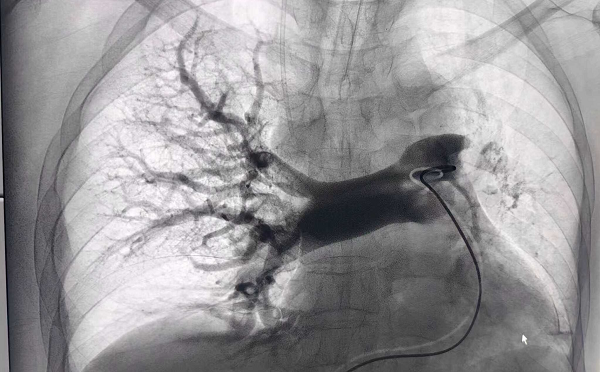

术后造影见右肺动脉大分支及主干充盈缺损消失,左肺动脉主干显影良好。